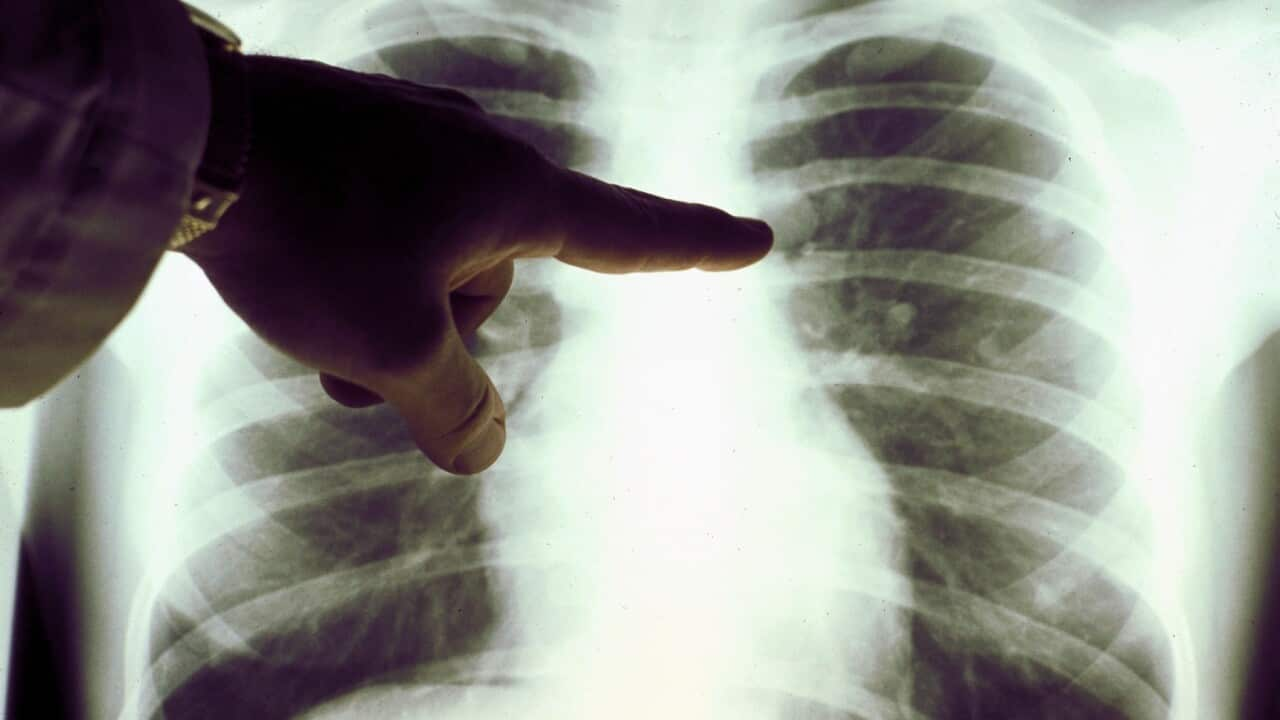

‘폐암 무료 선별 검사’는 호주에서 20년 만에 처음으로 시행되는 새로운 국가 암 검진 프로그램으로 흡연 이력이 있는 50세에서 70세 사이의 사람들이 대상입니다.

폐암은 호주에서 다섯 번째로 많이 진단된 암으로, 가장 많은 암 사망자를 발생시킵니다.